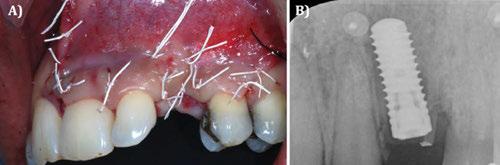

Continuación. A) Situación clínica tras 8 semanas de la extracción y cierre de tejidos blandos. Vista vestibular. B) Situación clínica tras 8 semanas de la extracción y cierre de tejidos blandos. Vista oclusal. C) Defecto óseo tras elevar un colgajo a espesor total. Vista vestibular. D) Defecto óseo tras elevar un colgajo a espesor total. Vista oclusal.

Figura 3. Caso clínico con membrana no reabsorbible (Goretex®). Continuación. A) Fresado para la colocación del implante. B) Colocación del implante en la posición tridimensional adecuada. C) Relleno del defecto óseo con `chips´ de hueso autólogo del propio paciente.

Figura 5. Caso clínico con membrana no reabsorbible (Goretex®). Continuación. A) Sutura y cierre primario. B) Situación radiográfica 2D inmediata post-operatoria.